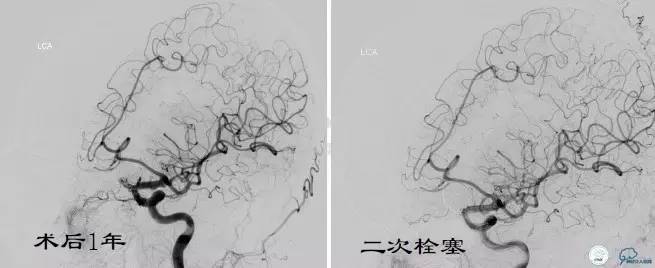

Case3 左ICA床突旁动脉瘤术后复发

复发

★2010年以前:复发率是7.6%~31.6%;

★2010年以后:复发率是5~30%;

★大多数研究认为6个月的复查对于发现动脉瘤复发是不够的,多建议每年一次复查;

★可能与该段动脉瘤的形态学特征和血流动力学因素有关。